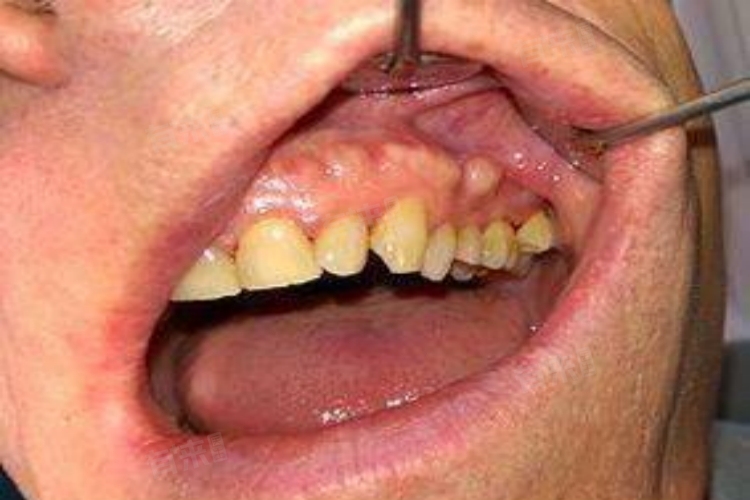

1、牙槽骨增生:牙槽骨受到长期的局部刺激,如不良修复体的压迫、慢性炎症刺激等,可能会导致牙槽骨骨质增生,形成硬的凸起。这种凸起一般质地坚硬,表面黏膜颜色正常,无明显疼痛。如果增生较小且不影响口腔功能和美观,通常无需特殊处理,定期观察即可。若增生较大,影响义齿佩戴、咀嚼或引起患者心理负担,可考虑手术切除增生的牙槽骨。手术在局部麻醉下进行,切除后创口缝合,术后需注意口腔卫生,预防感染。

- 应前往口腔科进行专业的口腔检查。医生会通过视诊和触诊观察凸起的形态、质地、位置以及是否伴有红肿、疼痛等症状。如果凸起位于牙槽骨区域,可能是牙槽骨增生或骨隆突,通常表现为硬质的骨性突起。